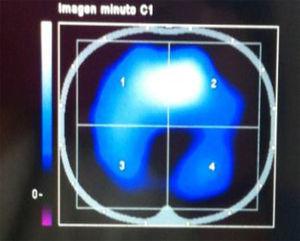

Presentamos el caso de un hombre de 24 años, que sufrió un traumatismo craneoencefálico (TCE), ingresando en una Unidad de Cuidados Intensivos (UCI) con un Glasgow Coma Score de 7 puntos. La tomografía axial computarizada (TAC) craneal mostró un hematoma extraaxial temporal izquierdo no subsidiario de cirugía (fig. 1). A continuación se realizó un dúplex transcraneal con codificación de color (DTCC) que confirmó la presencia de dicho hematoma, mostrando un tamaño de 45 x 9 mm (fig. 2). El hematoma extraaxial se pudo seguir en las siguientes 96 horas mediante DTCC a pie de cama sin apreciarse cambios en su tamaño. Se realizó entonces nueva TAC craneal que corroboró los hallazgos del DTCC. Posteriormente se pudo retirar sedación y extubar, encontrándose el paciente al alta consciente y sin focalidad neurológica.

Figura 2.

El DTCC permite el estudio estructural de los pacientes con TCE a pie de cama, en la Unidad de Neurocríticos, evitando los riesgos de un traslado a planta de radiología.